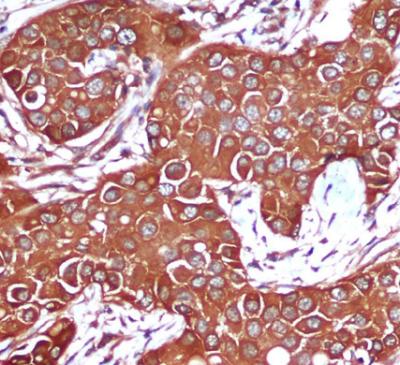

Immunohistochemical analysis of paraffin-embedded Breast cancer using AMPK beta 1 Mouse mAb (1/200 dilution).Antigen retrieval was performed by pressure cooking in citrate buffer (pH 6.0).